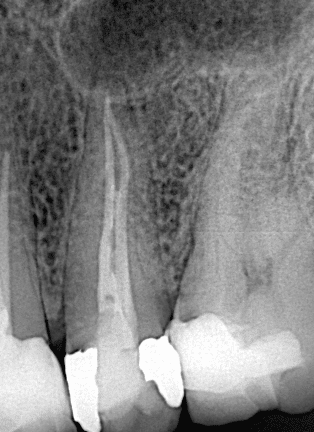

Immediate x ray after endo treatment

Post operative X ray after final result you can see the fitness of the filling